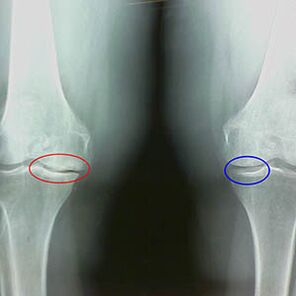

Određivanje stupnja artroze događa se X -RayOtkrivanje sudjelovanja u patološkom procesu koštanih struktura. Njihova promjena ukazuje da je mišićni sustav u neravnoteži već 5-10 godina. U pravilu ljudi Nekoliko godina osjećaju bolne bolove.

U prvoj fazi artroze, što se otkriva slučajno, dolazi do neznatnog povećanja kostiju. Rast se pojavljuje na mjestima najveće nestabilnosti zgloba. Tipično, pacijenti rijetko doživljavaju bol ili nelagodu tijekom kretanja.

Druga faza artroze smatra se lakim. Radiograf otkriva značajne kosti, ali hrskavica ne utječe. Količina sinovijalne tekućine je smanjena, ali simptomi boli pojavljuju se nakon dugog hodanja i trčanja, krutosti u zglobu i bolova pri savijanju i u položaju na koljenima.

Rana X -rada obilježja druge faze artroze koljena:

- šiljasti rubovi inter -picke tuberkula na tibiji, gdje je pričvršćen križni ligament;

- sužavanje zglobnog jaza na medijalnoj strani;

- Usmjereni rubovi kondila kostiju na medijalnim stranama, rjeđe u bočnom - ovisno o razvoju deformacije valgusa ili varijara.

Za drugu fazu u Larsenu Sužavanje zajedničkog jaza za više od 50% je karakteristično, ali to se može provjeriti samo u dinamici ili usporedbi s zajedničkim spojem.

Radiograf pokazuje prisutnost osteofita, promjenu u prostoru između kosti bedrene i tibije, što ukazuje na gubitak hrskavice u koljenu. Ponekad x -tray zglobova koljena pokazuje značajne znakove habanja hrskavice, ali pacijenti ne osjećaju značajnu bol.Naprotiv, artroza prve faze može poremetiti funkciju koljena, budući da su uzrok boli hipotonični mišići.